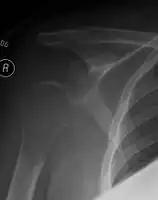

-

1.a. X-ray: solitary plasmacytoma upper arm near shoulder -

1.b. CT scan: solitary plasmacytoma upper arm near shoulder -